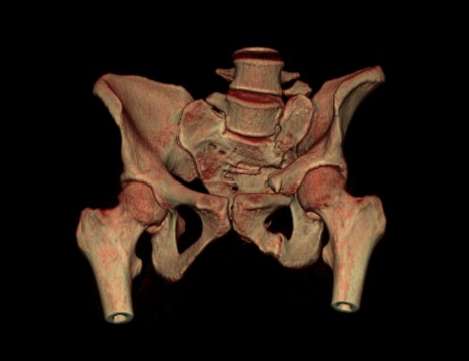

Застарелое повреждение таза

Уважаемые коллеги! Для определения тактики лечения выносим на обсуждение следующий клинический случаи: Пациентка К., 36 лет, находиться в отделении ортопедии НИИТО РК с диагнозом: Ложный сустав лонной и седалищной костей слева. Неправильно сросшийся перелом крестца слева. Сросшийся перелом лектевой кости слева. Металлоконструкция. Неправильно сросшийся перелом лучевой кости слева. Неправильно сросшиеся переломы н\3 обеих голеней.

з анамнеза:Со слов больной травма в результате падения с 4-го этажа 26.10.06. Находилась на лечении в городской больнице 26 г. Санкт-Петербурга с ДЗ: Сочетанная травма. Закрытый перелом левого предплечья с с\3, вывих лучевой кости.Открытый оскольчатый перелом дистальных метаэпифизов обеих костей левой голени. Закрытый оскольчатый перелом дистальных метаэпифизов обеих костей правой голени.Закрытый перелом лонной и седалищной костей слева. Перелом крестца слева. ЗЧМТ, СГМ. После выведения из депрессивного состояния 09.03.07 г операция: ЧКДО левой голени аппаратом Илизарова. 16.03.07 г.:остеосинтез левой локтевой кости стержнем, резекция головки лучевой кости.

На данный момент жалобы боли над лоном и КПС слева, а также в левом г\с суставе. Локально: Передвигается с помощью костылей. Движения в обоих г\с суставах качательные, болезненны. При пальпации отмечается болезненность в области лонной и седалищной костей слева.

Уважаемые коллеги мы выносим на обсуждение для определения тактики лечения застарелого повреждения таза. Как всегда есть 2 мнения "вести консервативно или оперировать", Если оперативный подход, то хотели бы узнать мнения коллег об объеме оперативного вмешательства.